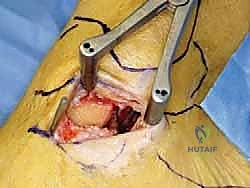

الإجراء الجراحي: إعادة بناء أربطة الكاحل الإنسية ورباط الدالية (خطوة بخطوة)

عندما يكون القرار الطبي هو التدخل الجراحي، فإن المرضى بين يدي الأستاذ الدكتور محمد هطيف يحظون بأعلى مستويات الرعاية الطبية المتاحة في اليمن. تُجرى هذه العملية المعقدة باستخدام تقنيات الجراحة المجهرية (Microsurgery) لضمان الدقة المتناهية، وغالبًا ما تُدمج مع استخدام مناظير المفاصل بدقة 4K لمعالجة أي إصابات غضروفية داخلية دون الحاجة لفتح المفصل بالكامل.

الخطوة الرابعة: تقييم وإصلاح رباط الدالية (Repair vs. Reconstruction)

بمجرد الوصول إلى رباط الدالية، يتم تقييم درجة التلف:

* الإصلاح المباشر (Direct Repair): إذا كانت أنسجة الرباط الممزقة ذات جودة جيدة (عادة في الإصابات الحديثة)، يقوم الدكتور هطيف بخياطتها مباشرة. يستخدم خطاطيف تثبيت عظمية (Suture Anchors) صغيرة جداً ومصنوعة من مواد متوافقة حيوياً (تذوب مع الوقت أو من التيتانيوم) لغرس الخيوط القوية في عظمة الكعب الإنسي، ثم يتم سحب الرباط الممزق وتثبيته بقوة في مكانه التشريحي الأصلي.

- إعادة البناء (Reconstruction): في الحالات المزمنة حيث يكون الرباط الأصلي قد تليف، تآكل، أو أصبح غير كافٍ للاستخدام، يلجأ الدكتور هطيف إلى تقنية "إعادة البناء". تتضمن هذه التقنية المتقدمة استخدام رقعة وترية (Graft)، إما من جسم المريض نفسه (Autograft - مثل أوتار الركبة أو وتر من القدم) أو رقعة صناعية متطورة. يتم حفر أنفاق ع